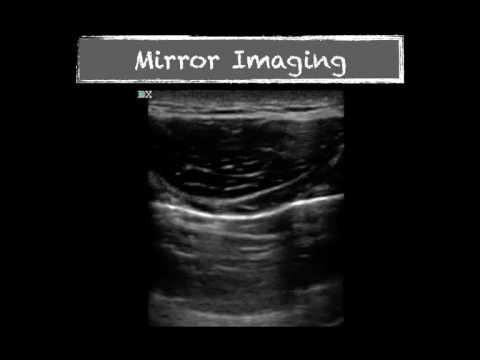

Video: Ultrasound Physics Imaging Artifacts

Video oleh POCUS Geek